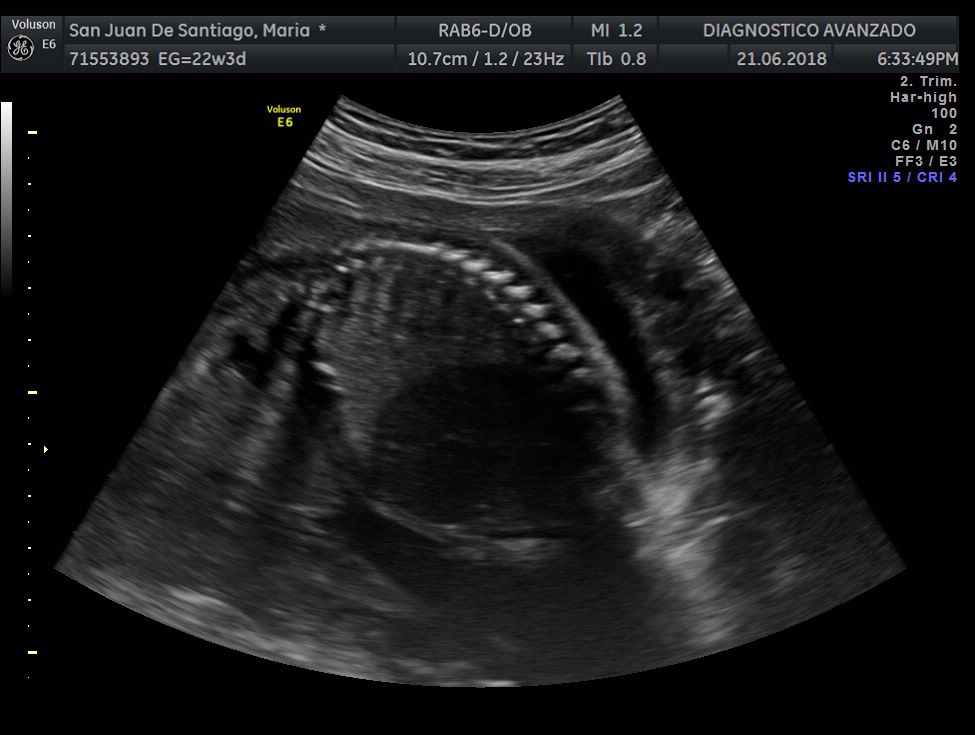

¡Hola a todos! Hoy hemos ido a hacer la tradicional ecografía 3D de la niña, os dejamos todo el material (aunque es un poco demasiado).